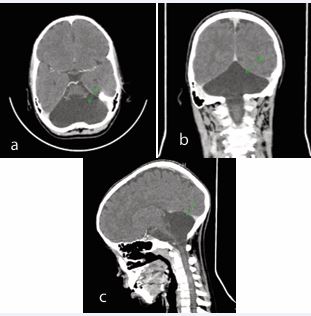

This case involves an 8-year-old girl with a history of inability to walk since birth. She was born at home and hospitalized for two days shortly after birth, with no major neonatal complications reported. Her developmental milestones were significantly delayed, as she achieved head control at 3 years and began speaking at 4 years. Her vaccinations were up to date. On examination, the patient appeared healthy and was in stable condition with normal vital signs. She showed no signs of systemic distress. Chest examination was clear, and heart sounds (S1 and S2) were normal, with no murmurs or gallops. The abdomen was soft and non-tender, with no palpable masses. Neurological assessment revealed a Glasgow Coma Scale (GCS) score of 15/15. Notable findings included spasticity and muscle atrophy in the lower extremities, although motor strength remained intact with a muscle power rating of 5/5 across all extremities. Tests for balance and coordination, including the Romberg test, rapid alternating movements, finger-to-nose, and tandem walking, were impaired. Meningeal signs were absent. Laboratory investigations, including a complete blood count, organ function tests, and random blood sugar levels, were within normal ranges. A pelvic X-ray was unremarkable. However, a non-contrast head CT scan revealed a complete absence of both cerebellar hemispheres, replaced by a cystic fluid component extending along the medulla oblongata. Minimal remnants of cerebellar peduncles were noted (Figure 1).

Figure 1 (a) Axial plane of contrast-enhanced CT scan of the brain complete absence of both cerebellar hemispheres replaced with cystic fluid component extending along the medullar oblongata (b) Coronal plane of contrast-enhanced CT scan of the brain (c) Sagittal plane of contrast enhance CT scan of the brain.